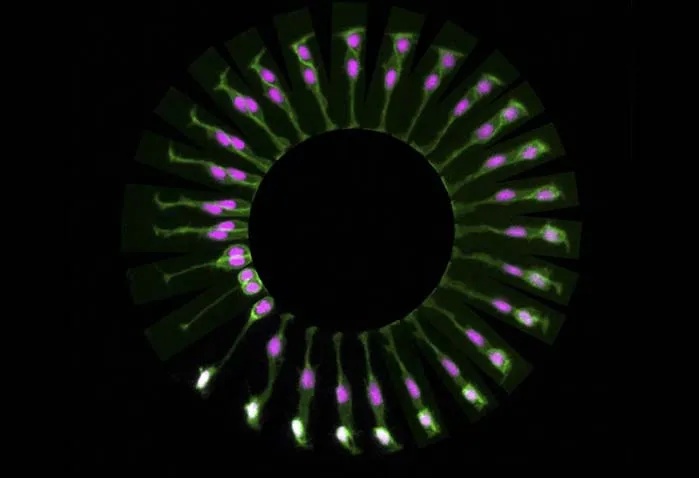

تقسیم سلول بنیادین در مغز

این تصویر الگویی دایرهشکل از مراحل مختلف تقسیم سلول بنیادین را در مغز یک گورخرماهی نشان میدهد. پهنای این دایره حدود ۲۵۰ میکرومتر (۰٫۲۵ میلیمتر) است و یک بازهی زمانی نه ساعته از پروسهی تقسیم سلولی را نشان میدهد.

این سلول در موقعیت ساعت هشت شروع به تقسیم شدن میکند و دو سلول متفاوت در مغز میسازد.